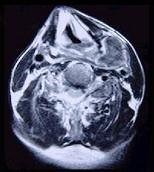

问题 男性,40岁,发现左侧颈部小包块,CT、MRI检查如图所示,请选择最可能的诊断()

选项 A.神经鞘瘤 B.神经纤维瘤 C.海绵状血管瘤 D.肿大淋巴结 E.副神经节瘤

答案 C